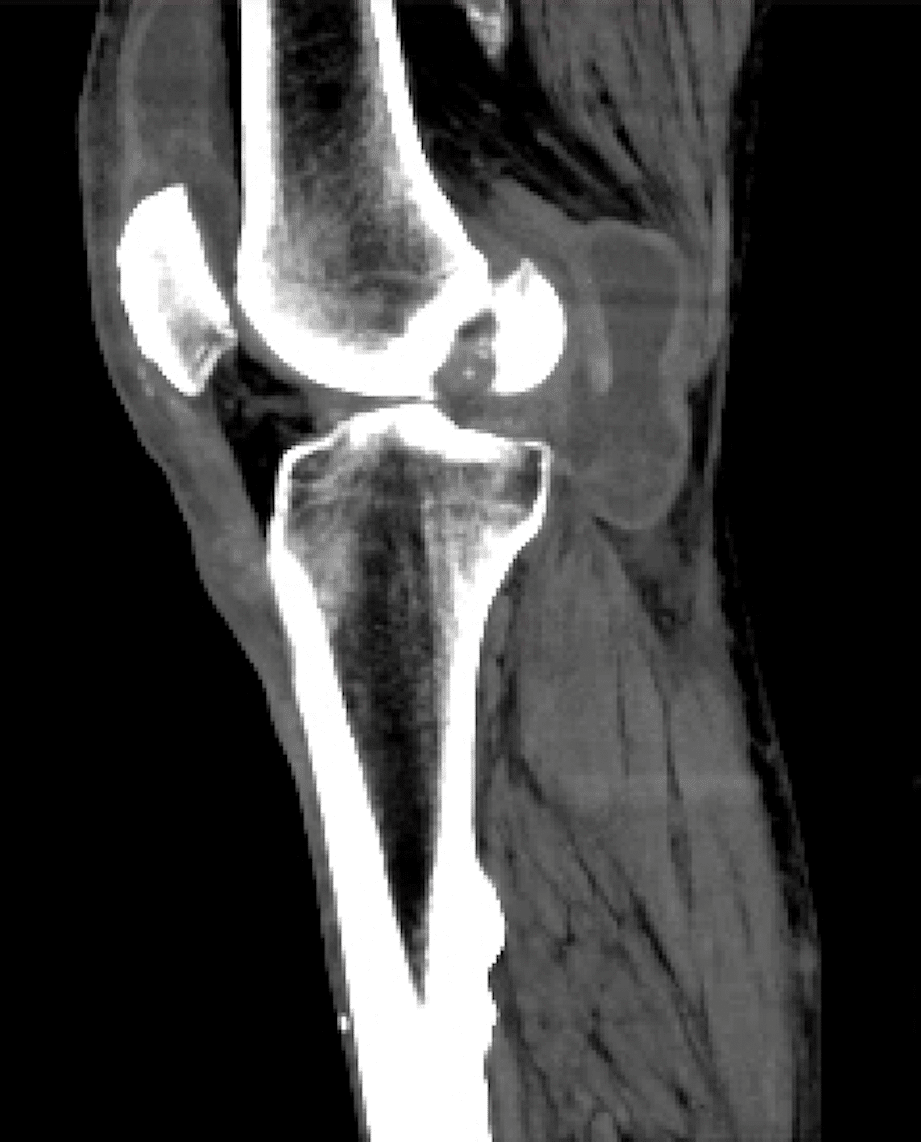

The diagnosis of cystic adventitial disease is suspected when pedal pulses disappear with knee flexion. Further diagnosis is made by imaging. MRI is probably the most sensitive method for the diagnosis of the sacs. It can assess the soft tissue and help in the differential diagnosis of soft tissue masses and compression. CT and duplex may also be useful for making the diagnosis. Arteriography is not a good way to make the diagnosis. This is because from the inside, the artery just looks like it has stenosis.

A Baker’s cyst is an accumulation of joint fluid from the knee. It accumulates behind the knee. Baker’s cyst may rupture and form a fluid sac that can be found behind the knee, in the popliteal fossa. Sometimes a Baker’s cyst may compress the popliteal artery. Such compression can cause leg pain when walking in a similar mechanism to entrapment. The diagnosis is usually made with duplex ultrasound. MRI can also aid in the diagnosis by showing the cyst compressing the artery. Treatment involves aspirating the Baker’s cyst.